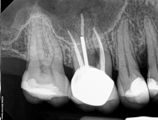

Treatment Examples

Conventional Treatment with Standard Core Restoration

Non-surgical endodontic treatment with resin core build up

Conventional endodontic treatment with alloy core build up

Conventional Endodontic Treatment with Post and Core Coronal Restoration

Conventional Endodontic Treatment/Retreatment with Prefabricated Bonded Post and Core

Conventional Endodontic Treatment with Minimal Clinical Crown: Cast Post and Core Coronal Restoration

Surgical Endodontic Treatment

Hemisection with Cast Post and Core

Surgical Exposure of ECIR with External Cervical Root Repair, Conventional RCT with Prefab Post

MB Root Amputation

Long Term CaOH Cases

12 Month CaOH Treatment

14 Months CaOH Treatment

All Treatment performed by Dr. Brian A. Christopherson